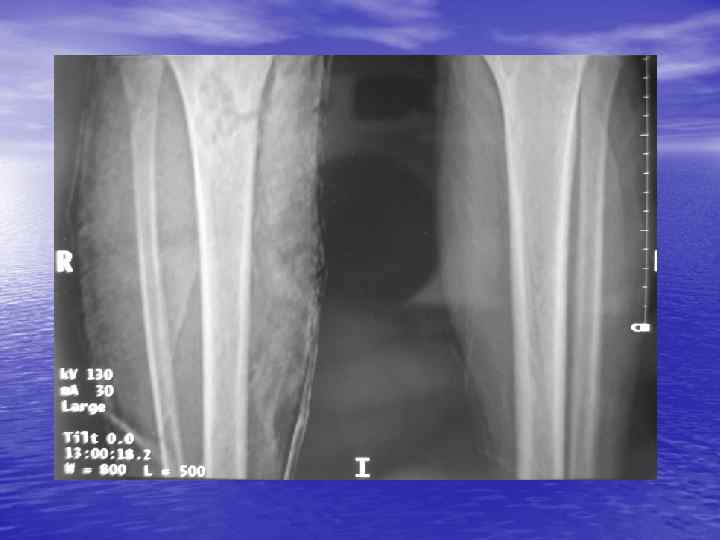

Структурный анализ Оценка основных макроскопических признаков: - положение - форма - размеры - характер контуров и структур патологически измененных участков

Структурный анализ

Денситометрический анализ Определение основных видов патологических образований: - обызвествленных - мягкотканных - жидкостных - жиросодержащих - воздухсодержащих